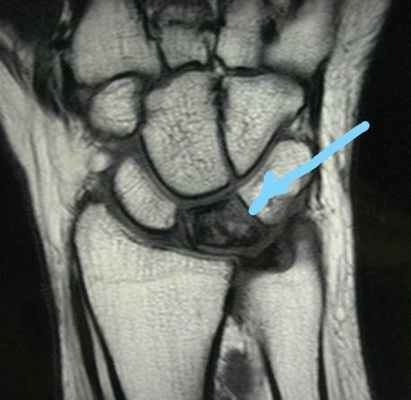

Некроз полулунной кости на МРТ

Большинство пациентов жалуются на боль запястье, усиливающуюся при нагрузке. При осмотре определяется болезненность в проекции полулунной кости. Первые шаги для диагностики болезни Кинбека — это сбор анамнеза, осмотр и рентгенограммы. Иногда требуются дополнительные исследования, наиболее информативным из которых является магнитно-резонансная томография. Именно МРТ позволяет выявить нарушение кровоснабжения полулунной кости, когда еще нет изменений на рентгенограммах. Также могут применяться компьютерная томография или остеосцинтиграфия.

В сомнительных случаях, когда рентгенография не позволяет с уверенностью говорить о диагнозе, выполняется КТ или МРТ:

МРТ при болезни Кинбека.

МРТ и КТ являются наиболее чувствительными при диагностике болезни Кинбека; простая рентгенография показывают отклонения позже, как правило, при начале склеротических изменений полулунной кости, сменяющихся кистозными изменениями, фрагментацией и коллапсом.